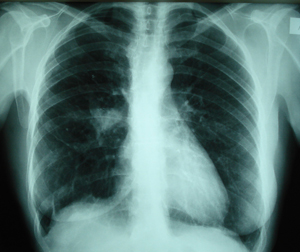

Εικόνα 4

Οπισθιοπροσθία ακτινογραφία θώρακος, δέκα έξι χρόνια μετά από την επέμβαση. Διακρίνεται σκίαση στην δεξιά πύλη. Μετά από βρογχοσκόπηση και βιοψία τέθηκε η διάγνωση καρκινοειδούς πνεύμονος.